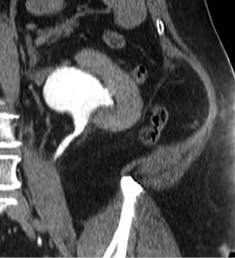

Pacientės parengimas operacijai nesiskyrė nuo kitų šlapimo takų operacijų. Šlapimo pasėlyje bakterijų augimo nenustatyta. Pooperacinės infekcijos profilaktikai operacijos metu skirta vienkartinė 1,0 g Cefazolino injekcija į veną, po operacijos skirta 960 mg Trimetoprimo ir Sulfametoksazolio du kartus per dieną per os. Operacija atlikta esant bendrinei nejautrai. Operacinėje ligonė paversta ant dešiniojo šono, kūno padėtis paruošta juosmeniniam pjūviui. Atliktas kairysis lumbotominis pjūvis, jį pratęsiant į 11 tarpšonkaulinį tarpą. Išorinis ir vidinis įstrižiniai pilvo raumenys prapjauti naudojant elektrokaustiką. Skersinis pilvo raumuo praskirtas bukuoju būdu. Pilvaplėvė atidalyta išsaugant jos vientisumą. Retroperitoniniame juosmeniniame tarpe praskirtas riebalinis audinys. Išdalytas šlapimtakis, jis pakeltas ant laikiklio. Šlapimtakis proksimaliniame segmente buvo standus, padengtas fibrozine kapsule, priaugęs prie riebalinio audinio ir didžiojo juosmeninio raumens. Bukuoju ir aštriuoju būdais šlapimtakis atidalytas nuo gretimų struktūrų, mobilizuotas apatinis kairiojo inksto polius. Kairiojo inksto geldelė ryškiai išplėsta, pripildyta šlapimo, negalinti išsituštinti dėl proksimalinio šlapimtakio striktūros. Šlapimtakio visceralinė sienelė įpjauta išilgai per visą striktūros ilgį. Šlapimtakio pjūvis atliktas nuo geldelės, išilgai per susiaurėjusią šlapimtakio dalį distaline kryptimi iki plataus šlapimtakio spindžio. Įvertintas susiaurėjimo ilgis – 5,5 cm. Pašalintas senas šlapimtakio stentas, naudojant stygą į šlapimtakį įkištas naujas 6 Ch 28 cm ilgio ilgalaikis stentas. Šlapimtakio pjūvio krašteliai persiūti Vicryl 3/0 siūlėmis (laikikliais) (1 pav.).

1 pav. Kairiojo šlapimtakio plastika, operacinis vaizdas (KI – kairysis inkstas)

2019 m. gegužės 7 d. (praėjus apie 6 mėn. po operacijos) atlikta kompiuterinė tomografija (4 pav. B). Kairiojo inksto kolektorika kiek prasiplėtusi, geldelė iki ~42 mm pločio, kontrastinę medžiagą (k/m) skiria laiku, kontrastuojasi, k/m nuteka šlapimtakiu į šlapimo pūslę. Kairysis šlapimtakis neprasiplėtęs, proksimalinėje dalyje jo spindis iki 5,5 mm diametro, distalinėje dalyje – iki 7 mm. Ties šlapimtakio proksimaline dalimi matyti infiltruoti aplinkiniai audiniai (vertinama kaip pakitimai po buvusios operacijos). Kitų pakitimų šlapimo takuose nenustatyta.

2019 m. spalio 9 d. (praėjus apie 12 mėn. po operacijos), atlikus kompiuterinę tomografiją, matyti, kad kairiojo inksto geldelė mažiau išplėsta – iki ~26 mm pločio (buvo iki 42 mm), PUJ spindis – apie 2,5 mm pločio, distaliau šlapimtakis neišplėstas, jo spindis iki pat šlapimo pūslės išmatuojamas 3,5–5 mm, sienelės plonos, rentgenokontrastinių akmenų nematyti (4 pav. C). Ties PUJ periureteriniuose audiniuose – fibroziniai pakitimai, perinefriniuose audiniuose – dorzaliai riebalinio audinio ribotos pooperacinės sankaupos.

A

B

C

4 pav. Kompiuterinė tomografija (A – prieš operaciją; B – praėjus 6 mėn. po operacijos; C – praėjus 12 mėn. po operacijos)